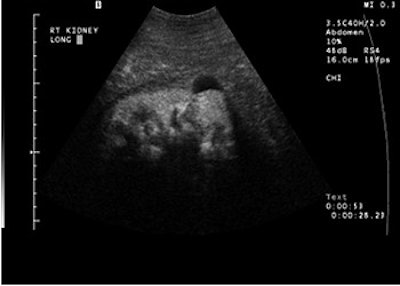

A large renal cell carcinoma on pre-contrast ultrasound (above). After injection of the contrast agents (below), there is enhancement. Individual vessels in this renal cell carcinoma can be picked out; the mass also is enhancing more than the normal renal cortex. "If we increase the mechanical index, we can actually eliminate most of the parenchymal phase and actually look at discrete vessels," Barr said. Images courtesy of Dr. Richard Barr, Ph.D.

Part of the group’s sonographic technique is to increase the mechanical index, eliminate most of the parenchymal phase, and look at discrete vessels.